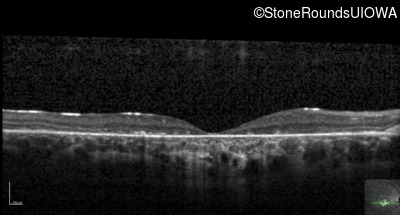

Optical Coherence Tomography - Left - 10/125

Exemplar / OCT Stack

OCT Stack